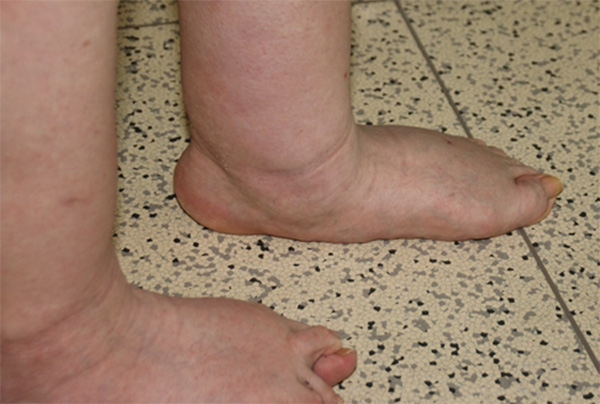

Single/Double-Heel-Rise-Test

Der Patient wird aufgefordert zunächst mit beiden Fußen in den Zehenstand zu gehen (Double-Heel-Rise-Test). Im Zehenspitzenstand kommt es zu einer physiologischen Varisierung der Ferse als Zeichen der Verriegelung des Rückfußes mit Stabilisierung der Rückfuß-Vorfuß-Beziehung. Kommt es nicht zu der genannten Varisierung der Ferse ist der Test als pathologisch zu bezeichnen 1. Der Double-Heel-Rise-Test dient vor allem der Beurteilung der Rückfußbeweglichkeit. Anschließend ist ein einbeiniger Zehenspitzenstand durchzuführen. Die funktionellen Anforderungen an den Rückfuß sind im Einbeinstand wesentlich höher als im Double-Heel-Rise-Test. Überprüft wird ob der Zehenstand erreicht wird und ob es zu einer Rückfußvarisierung kommt. Ergänzend kann geprüft werden, ob der Patient mit Unterstützung des anderen Beins einen Zehenspitzenstand erreichen und dann einbeinig halten kann.

Abbildung 4: Der Patient steht auf einem Bein an einer Wand und kann sich Abstützen um die Balance zu halten (links). Das kontralaterale Bein wird angehoben (mitte). Der Patient wird aufgefordert in den einbeinigen Zehenstand zu gehen. Dabei kommt es zu einer Rückfußvarisierung (rechts) (J. Dohle).

Abbildung 5: Bei schwerer Planovalgus-Deformität in Folge einer Tibialis-posterior-Dysfunktion kommt es im Zehenstand zu keiner Rückfußvarisierung (J. Dohle)